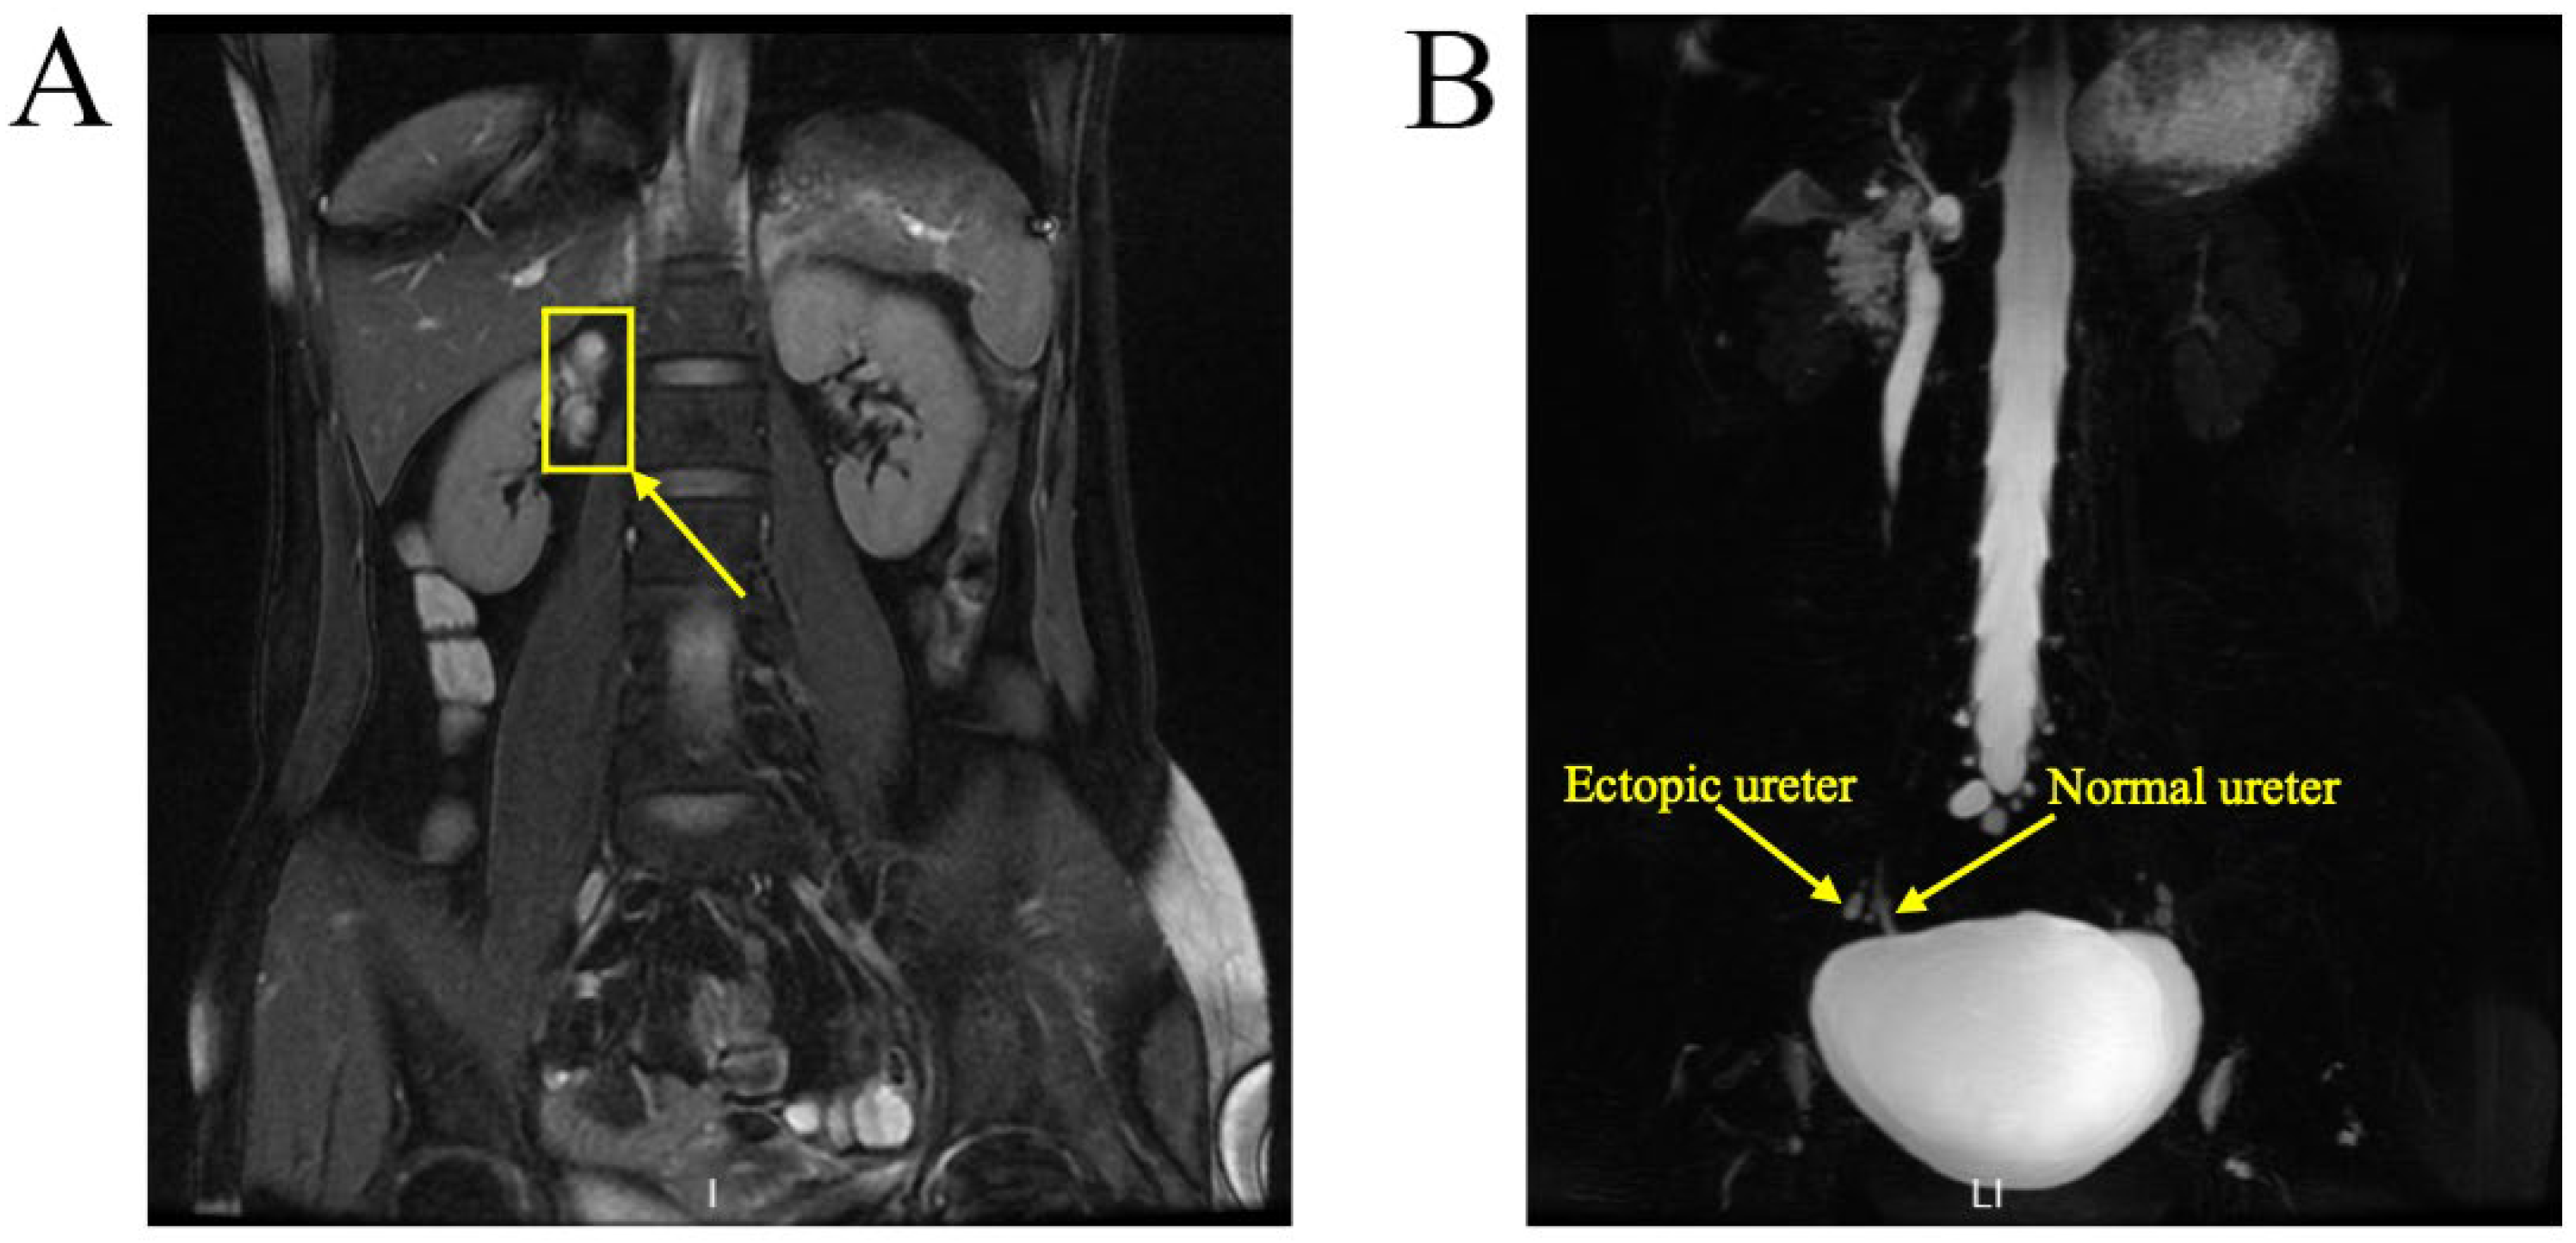

A 37-year-old woman was referred to our hospital for persistent vaginal discharge. After she underwent vaginal cyst excision 11 years ago, she began to experience persistent vaginal discharge, requiring two sanitary pads daily. A pelvic examination revealed a pinpoint-like hole in the right anterior wall of the vaginal fornix. It was observed that clear fluid was leaking from the hole, and a 3-centimetre in diameter cystic mass was palpated nearby. An MRU demonstrated that the duplicated renal pelvis was located at the upper pole of the right kidney. The left kidney and ureter were normal (Figure 8A). An MRU also revealed the dilated upper segment, thinned middle segment, and slightly expanded lower segment of the right duplicated ureter. Additionally, the distal segment of the duplicated ureter was enlarged to 1.7 × 1.3 cm, terminating at the right wall of the vagina. (Figure 8B). Consequently, the right ectopic ureter was separated at its base and reimplanted into the bladder.

Figure 8.

MRU demonstrated a duplex collecting system. (A) The duplicated renal pelvis (yellow arrow) was located at the upper pole of the right kidney. (B) The duplicated ureter (yellow arrow) drained into the right wall of the vagina.